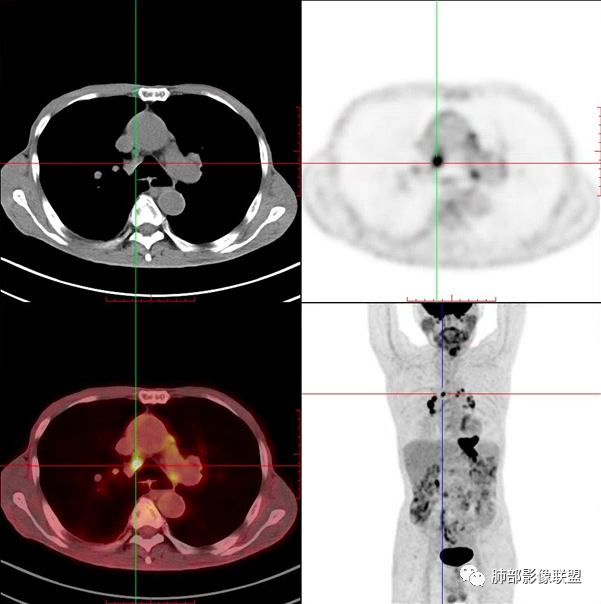

病理结果:小细胞肺癌

关于小细胞肺癌

小细胞肺癌(Small Cell Lung Cancer,SCLC)约占肺癌的15%-30%,起源于支气管粘膜或腺上皮内的Kulchitsky细胞(嗜银细胞),是一种小细胞组成的恶性上皮肿瘤,恶性程度极高、转移早、易复发、预后差、放化疗敏感。

2娘小崽大、淋巴及血行转移早、冰冻纵隔及肺门、血管脂肪间隙消失

因为病灶侵袭力强,病灶易沿淋巴道、间质及心血管间隙等结构侵犯并密切挤压上述结构,常常能够观察到脂肪间隙消失。易于出现冰冻纵隔。原发灶与肺门转移灶可形成哑铃状外观,甚至转移灶体积大于周围原发灶,有人称之为“娘小崽大”。早期病灶有时很小甚或隐匿,仅能看到转移灶,或转移淋巴结与原发灶融合分界不清。病变向肺门延续的串珠样淋巴结转移也是SCLC的典型特点。